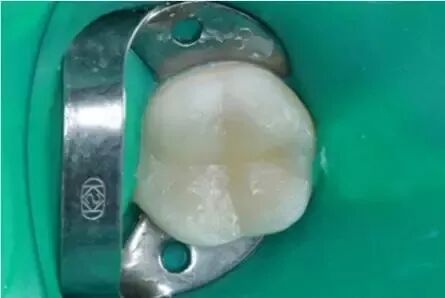

UcYdeH及IUXgAaXhNpgbG

封氫氧化鈣一周

一周後根管充填

去淨暫封物後樹脂充填